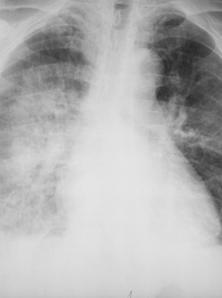

Fig. 12 – Staza pulmonara (opacitati vasculare intercleidohilar, hiluri cu dimensiuni si opacitate crescute, difuz conturate, diminuarea difuza a transparentei pulmonare, mai ales pe dreapta)